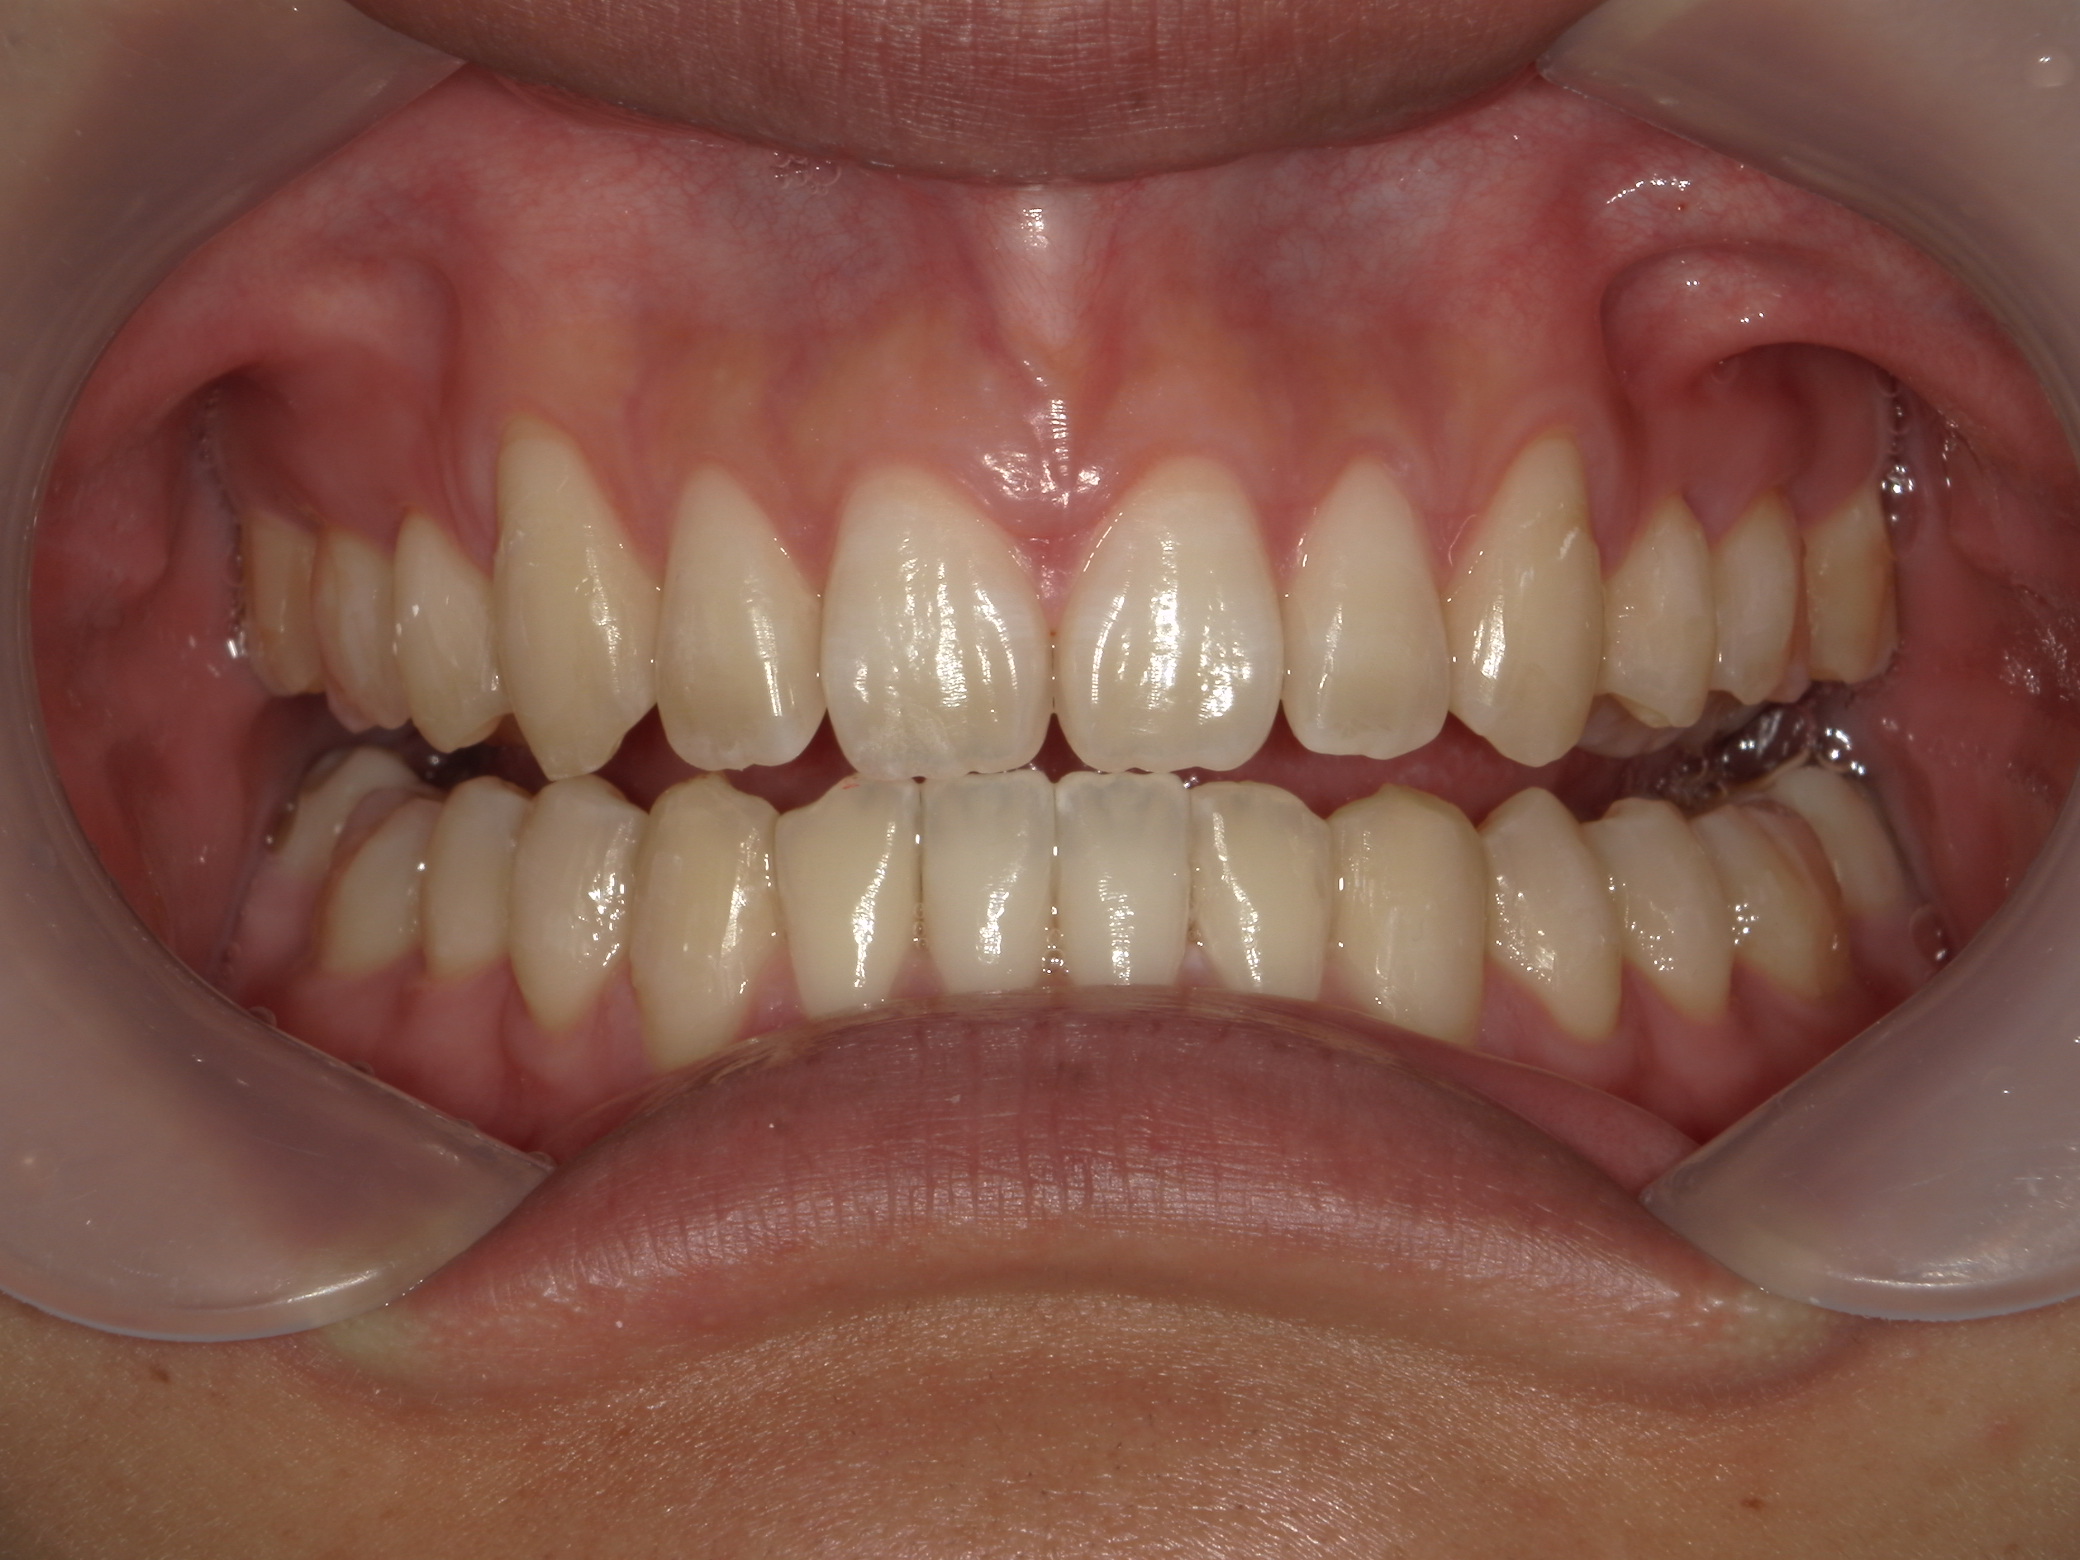

インビザライン矯正 症例(24)

主訴: 前歯の隙間が気になる。

カテゴリー : 隙間がある(空隙歯列)